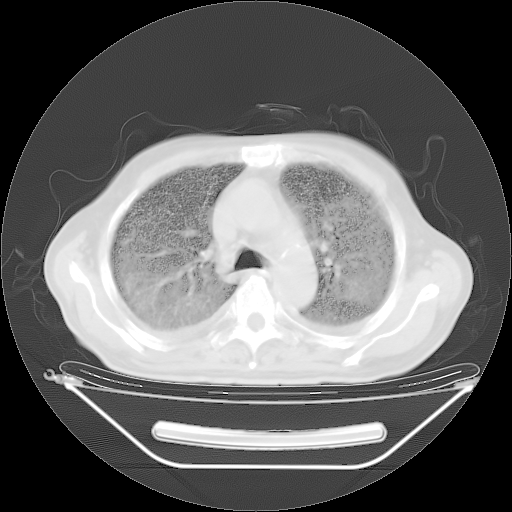

今天复查肺部CT,发现双肺广泛磨玻璃样改变。所以我把3月19日和5月9日相隔50天的肺部CT上传。请大家会诊。

2009年3月19日肺部CT片。

2009年3月19日肺部CT